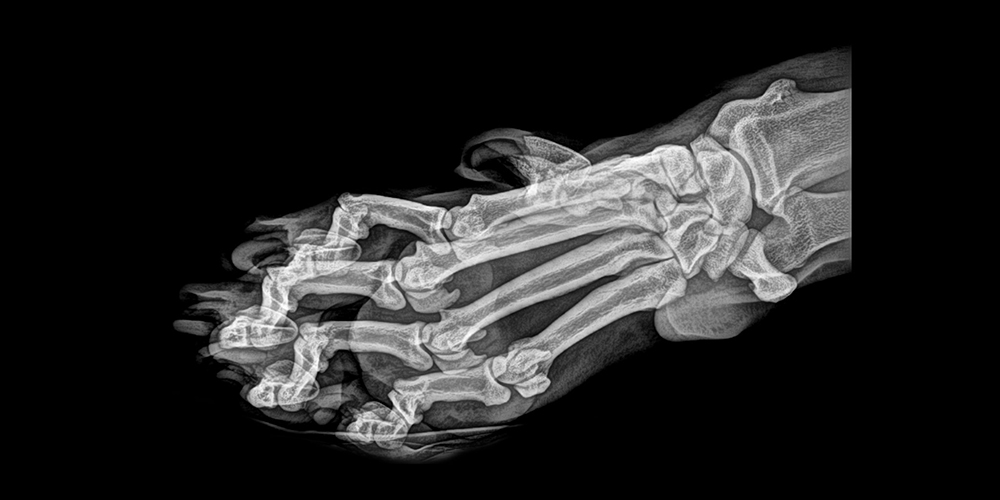

3. 美国俄勒冈动物园年度体检:X射线下的动物们

据美国俄勒冈动物园(Oregon Zoo)10月29日推文,动物园兽医中心的健康检查中也包括X射线检查,这些检查揭示出了动物们的“内在美”。俄勒冈动物园每年都会例行进行这样的动物体检,同时,动物园也放出了各种动物的“露骨”照,被媒体报道。